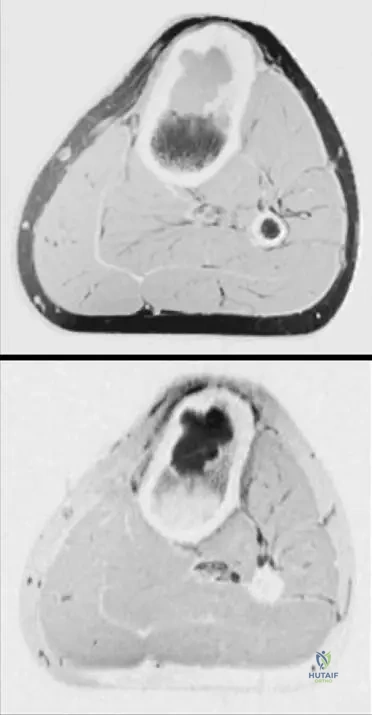

Correct Answer: C

Rationale: The clinical context for Fig. 8.49 explicitly states that the tissue of a chondromyxoid fibroma often resembles hyaline cartilage, which is typically described as gelatinous and bluish-white. The image itself shows a glistening, somewhat translucent appearance consistent with cartilage. The other options describe appearances more typical of other bone tumors (e.g., osteosarcoma, lipoma, giant cell tumor).

A 19-year-old male presents with localized pain and swelling in his left metacarpal. Radiographs confirm a lytic lesion. An intraoperative image of the resected specimen is shown. What type of tissue does the gross appearance of chondromyxoid fibroma typically resemble?

View Answer & Explanation

Rationale: The clinical context for Fig. 8.49 explicitly states, "The tissue often resembles hyaline cartilage." This is a direct factual recall from the provided text. The image itself shows a glistening, somewhat translucent appearance consistent with cartilage.